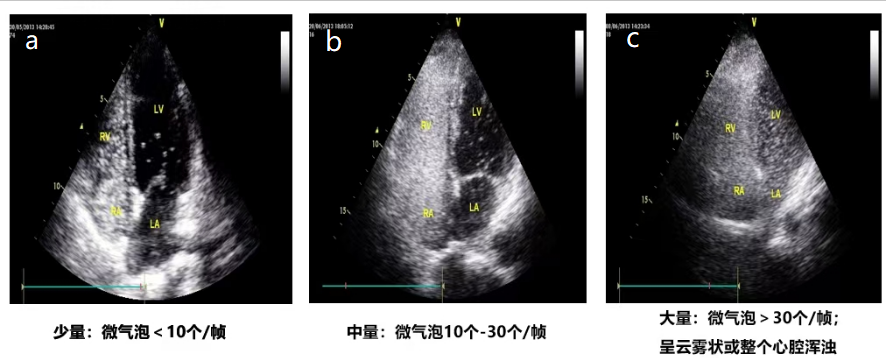

图片展示了右心声学造影右向左分流的半定量评估情况。图a为1级少量分流,左心房微气泡小于10个/帧;图b为2级中量分流,左心房微气泡小于10-30个/帧;图c为3级大量分流,左心房的微气泡数量大于30个/帧。